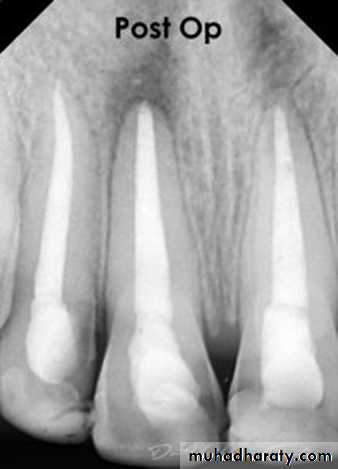

Obturation is the method used to fill and seal a cleaned and shaped root canal using a root canal sealer and core filling material.1

1- To obtain tight seal (apically and coronally) by total obliteration of the root canal space.

1. Easily introduced into the root canal.2. Seal the canal laterally ,apically and coronally.

5. It should be radiopaque.